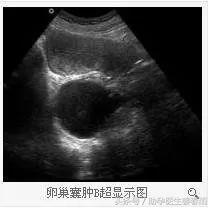

结果如下:子宫内0.2x0.2cm,右侧卵巢囊肿6.1x5.1Cm

一、超声检查